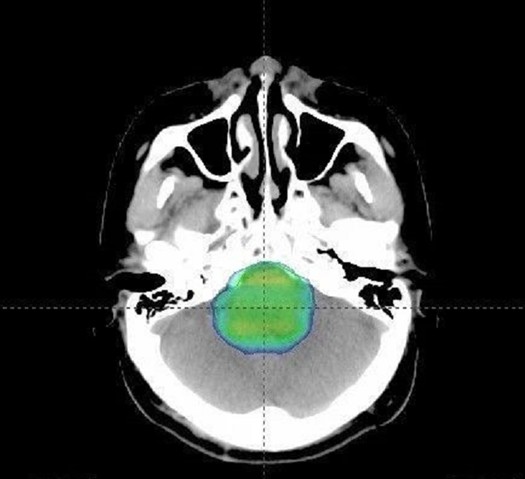

你的神经外科医生可以在手术过程中的任何时候使用MRI技术来帮助团队确定是否全部的肿瘤组织都被切除了。如果有肿瘤组织残留,你的外科医生可以继续手术切除它。

在手术过程中使用MRI重新评估肿瘤,可以使神经外科医生精确地操作,并巧妙地处理可能出现的并发症。